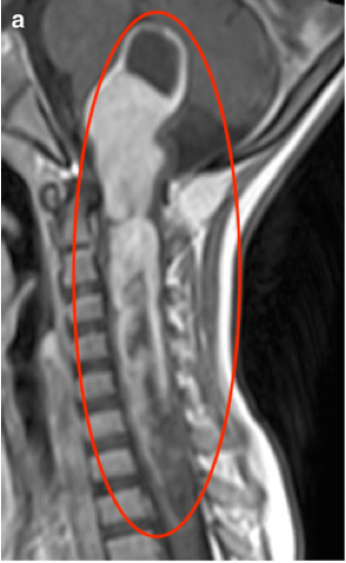

圖b、c:b、 c術(shù)中矢狀位和軸向T1加權(quán)MRI圖像。腫瘤切除后,iMRI檢查發(fā)現(xiàn)殘留病灶仍在右側(cè)C1-C2水平(軸切面),術(shù)中再次手術(shù)切除。

術(shù)中MR檢查和術(shù)前MRI相比,結(jié)果顯示在右側(cè)C1-C2水平的對比增強(qiáng)區(qū),顯示有少量腫瘤殘留(圖b,c)。再次無菌消毒、鋪巾后,對這些有殘留腫瘤的節(jié)段再次鏡下檢查,發(fā)現(xiàn)殘留病變并切除。在細(xì)致的止血后,再次行術(shù)中MR檢查,證實(shí)病變被完全切除。較后行顱骨成形術(shù)及椎板原位復(fù)位術(shù)。